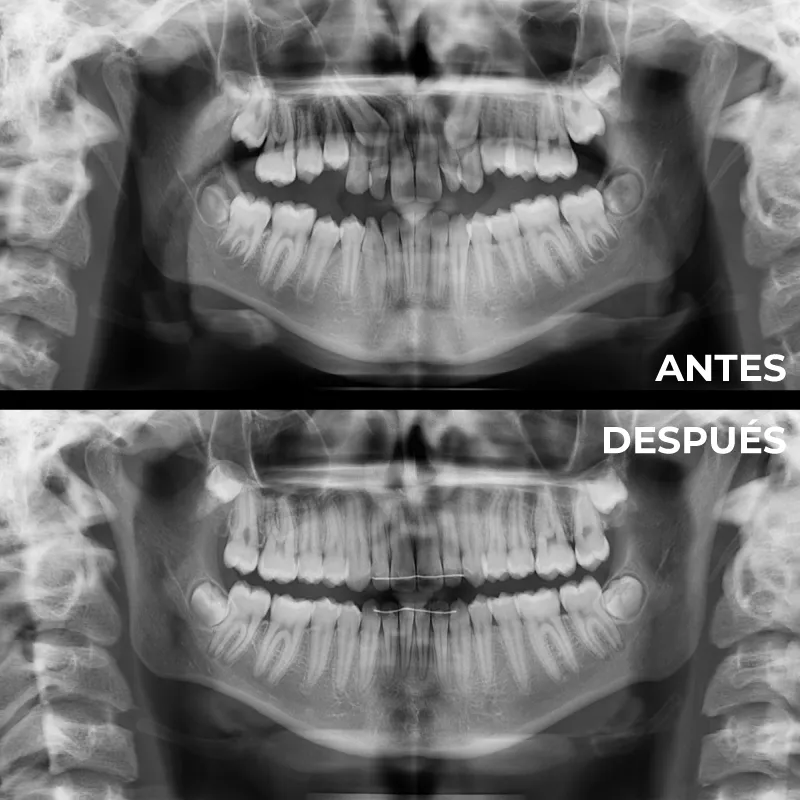

Donde realizamos una primera visita, una historia clínica, tomamos una serie de fotos extra e intraorales y realizamos unas radiografías para poder con toda esta información estudiar cada caso individualizado por todo nuestro equipo de profesionales.